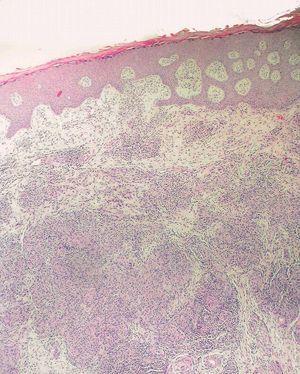

Los datos de laboratorio al ingreso incluyeron un recuento de CD4 de 26 células/ml, una carga viral de 740.000 copias/ml y una radiografía de tórax que fue normal. Se llevó a cabo una artrocentesis que mostró un líquido articular inflamatorio con baciloscopia y cultivo negativos y una radiografía de rodilla izquierda que fue normal. Se extrajeron hemocultivos que fueron negativos. En el estudio histológico de dos lesiones nodulares se objetivó, bajo una epidermis con acantosis, inflamación y reacción granulomatosa dérmica superficial y profunda inespecífica, constituida por granulomas no supurativos mal delimitados con presencia de linfocitos e histiocitos epitelioides sin células gigantes (figs. 3 y 4). Los cultivos microbiológicos de las muestras cutáneas fueron negativos, observándose numerosos bacilos ácido-alcohol resistentes en ambas muestras (fig. 5), siendo negativa la reacción en cadena de la polimerasa (PCR) para Mycobacterium tuberculosis.

Figura 3. Inflamación y reacción granulomatosa bajo una epidermis hiperplásica. Hematoxilina-eosina, x400.

Figura 4. Granulomas sin necrosis constituidos por linfocitos e histiocitos epitelioides. Hematoxilina-eosina, x100.

Histológicamente no se observan diferencias entre las infecciones causadas por las diferentes especies de micobacterias atípicas11. El examen microscópico de las lesiones cutáneas muestra una dermatitis granulomatosa profunda, con o sin necrosis caseosa, que a menudo se delimita mal y compromete el panículo adiposo en los pacientes con sida. El tiempo de evolución influye notablemente en el patrón histopatológico, especialmente en el paciente inmunodeprimido. Las lesiones iniciales muestran un infiltrado inflamatorio predominantemente neutrofílico o mixto, que incluye granulocitos, linfocitos, monocitos, y ocasionalmente, células gigantes multinucleadas y macrófagos espumosos. Las lesiones más evolucionadas muestran una reacción inflamatoria granulomatosa. Es habitual la demostración de bacilos ácido-alcohol resistentes con tinciones específicas en el paciente inmunodeprimido12.